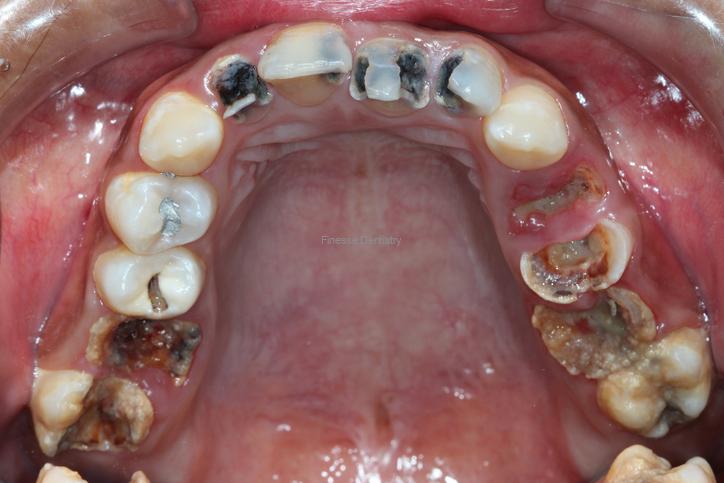

- Extensive Decay: We love a good “save,” but if a cavity has traveled below the gum line or destroyed too much structure, the tooth may no longer be restorable.

- Periodontitis (Advanced Gum Disease): This condition affects the underlying bone. If it progresses, teeth become loose and cause swelling. Unlike a cavity that usually affects one tooth, gum disease often impacts the whole mouth. We use 3D CBCT scans to evaluate every tooth. If the situation isn’t clear, we always attempt a “saving protocol” (such as deep cleaning) and monitor the results before moving toward an irreversible extraction.

- Failed Root Canals: Root canals have a success rate over 90%. However, if a re-treatment or surgical intervention fails, extraction is the final step to eliminate infection. (Rao S et al. (May 10, 2023) Incidence of Endodontic Failure Cases in the Department of Conservative Dentistry and Endodontics, DY Patil School of Dentistry, Navi Mumbai. Cureus 15(5): e38841. doi:10.7759/cureus.38841)

- Cracks and Trauma: Think of a tooth like a fine ceramic; it is strong but can crack under pressure. This risk is higher for patients who grind their teeth or have large, older fillings. While minor cracks can be managed with a crown, a deep vertical crack usually means the tooth must be removed.